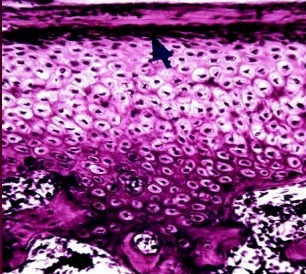

18

Q

A

articular disc of young adult

19

articular disc of elderly adult